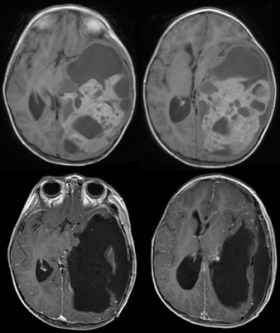

- de connaître la localisation et la taille de la tumeur

- de connaître son extension exacte, son caractère infiltrant ou non, métastatique ou non

- d’évaluer son retentissement cérébral (HTIC, hydrocéphalie, effet de masse, engagement)